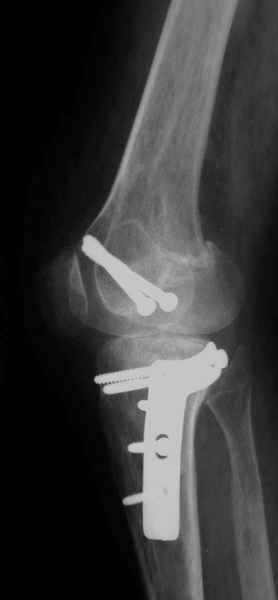

Уважаемый Евгений ! Спасибо за ответ, но мне представляется, что в нашем случае основной проблемой является не столько прогрессирующий вальгус конечности, сколько несросшийся перелом мыщелка бедра и дефект мыщелка большеберцой кости - вероятно первичная репозиция выполнялась без пластики.

Мы обсуждали вопрос первичного протезирования коленного сустава. На мой взгляд, данная больная не лучший кандидат для этого метода - большой дефект мыщелка бедра потребует первично использовать ревизионный протез. Обсуждался и вариант, аналогичный предложению В.Е.Казеннова - постепенное исправление деформации (вероятно с остеотомией голени) - большие сомнения в эффективности из-за наличия дефекта мыщелка б\б кости, расчет только на наличие в суставе массивнй рубцовой интерпонирующей "подушки".

Относительно "рубцовой подушки" я имел в виду остатки мениска ( частично вколоченного в дефект мыщелка и фрагменты хряща), все таки на рентгенограммах суставная щель в этом отделе чем то заполнена. Что касается некроза мыщелка бедра, то мне кажется он уже наступил - томограмма ноябрь5.

С учетом всего сказанного - наличия прогессирующего вальгуса конечности, довольно приличного объема движений, имеющегося, вероятно, некроза мыщелка бедра, наиболее рациональным представляется удалить пластину с б\б кости, произвести остеотомию б\б кости с коррекцией вальгуса, разгрузив тем самым наружный отдел сустава, и синтезировать фрагменты голени накостным фиксатором. Максимально тано начать восстановление движений в суставе. Скорее всего рано или поздно речь о протезировании всеже возникнет, но мы хотя бы будем иметь приличную ось конечности.